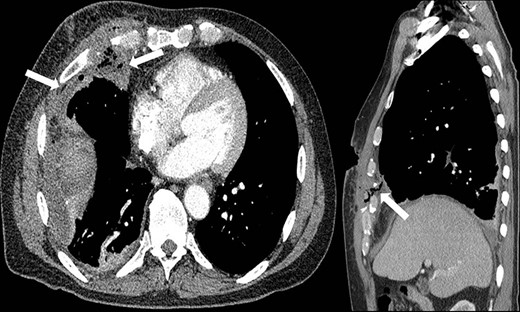

Representative axial and sagittal images from the patient’s CT scan on Day 7 after initial operative intervention. The white arrows on both images show subcutaneous and intrathoracic air, concerning for an empyema.

Subsequent review of bean bag projectiles and discussion with the law enforcement officers monitoring the patient revealed that the bean bag projectile included nonmetal components. Out of concern for infection risk, the surgical team performed video-assisted thoracoscopic surgery (VATS) on hospital Day 3 whereby the projectile was successfully removed (Fig. 3). Upon intra-operative inspection, the right middle lobe was contused but not actively bleeding, so no further intervention was performed, and a new chest tube was placed. On post-operative day (POD) 3, the chest tube was removed; however, on POD 6 purulent drainage was observed from the previous bean bag entry wound, and laboratory evaluation revealed a leukocytosis to 21.0 K/mm3. The clinicians irrigated the wound at the bedside and initiated antibiotics treatment. Due to persistent leukocytosis and drainage of purulent fluid from the wound, the clinicians obtained a CT scan on POD 7, which showed a complex right pleural effusion that communicated with a small pocket of fluid in the chest wall, concerning for an empyema (Fig. 4). The following day, the surgeons performed VATS decortication, removing a significant amount of purulent pleural fluid and fibrinous exudate and placing two chest tubes. Culture of the pleural fluid grew Staphylococcus aureus. By POD 11/3, the patient had a persistent right-sided effusion, which the team treated with intrapleural tPA/Dornase infused via previously placed chest tubes. By POD 20/12, the patient’s leukocytosis and right-sided effusion had resolved, and both chest tubes were removed. He was discharged the subsequent day and has not returned to our facility since then.